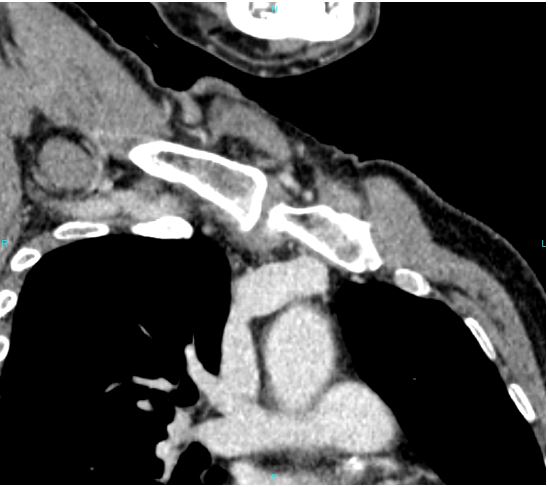

การตรวจฉีดสีหลอดเลือดดำโดยเทคนิคเอกซเรย์คอมพิวเตอร์ (CT venography) หากสงสัยหลอดเลือดดำส่วนกลางอุดตัน

ภาพแสดงการตรวจฉีดสีหลอดเลือดดำโดยเทคนิคเอกซเรย์คอมพิวเตอร์พบหลอดเลือดดำลึกในอกตีบตัน (Right innominate vein occlusion)